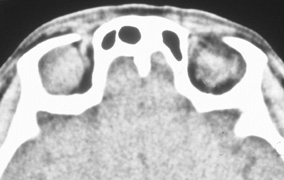

Figure 10. A. Large, well-encapsulated intraconal mass on MR scan. B. Small lateral canthotomy incision will be used to perform lateral orbitotomy and remove the intraconal mass.